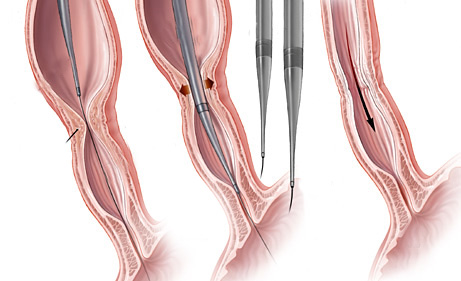

- Dilatadores flexíveis: uma série de sondas graduadas (espessura crescente) chamadas de sondas termoplásticas podem ser usadas. Estes são tubos que passam através do esófago para o estômago. Os tubos utilizados tornam-se progressivamente maior, até que o tamanho desejado seja atingido

- Balões dilatadores: a dilatação do esôfago pode ser feita usando balões durante a endoscopia. A endoscopia flexível permite ao examinador visualizar diretamente a estenose. Um balão é introduzido pelo canal do aparelho até a zona de estreitamento. Ele é então insuflado com água até uma certa pressão, que é pré-ajustada para uma dada circunferência. Quando insuflado, torna-se em forma de salsicha, esticado, e faz com que a estenose se abra.

Tratamento da Acalasia

- A Acalasia requer um tipo de balão específico, mais longo e maior, chamado de balão pneumático. Nesta situação, as fibras musculares espásticas na parte inferior do esôfago são esticadas.

Estenoplastia

Em algumas ocasiões, o estreitamento (estenose) é tão grande que nem os instrumentos de dilatação conseguem passar. Nestes casos e em algumas outras situações, realiza-se o procedimento de estenoplastia. Este consiste na realização de pequenos cortes na região da estenose com auxílio de um estilete que é passado pelo canal de trabalho do endoscópio. Estes pequenos cortes ajudam abrir o estreitamento facilitando a passagem dos dilatadores e acelerando o processo do tratamento. Em alguns casos após a realização dos pequenos cortes algumas substâncias, como corticóides, são injetadas na região para prevenir que o estreitamento feche novamente com facilidade.